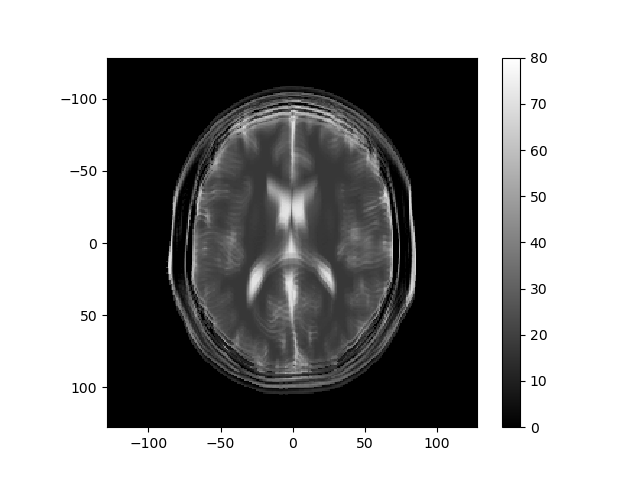

The left image below shows the magnitude of the k-space data obtained for an MRI, and the right image shows the reconstructed image.

Consider how the image would change if the k-space data were multiplied by \sin^2(\cdot) or \cos^2(\cdot) of k_r or k_c. Below are several k-space representations that have been distorted in this way. In each case, assume that only the magnitude of the k-space data is changed. Match each k-space image with the corresponding reconstructed image, and enter your results from the corresponding pull-down list.